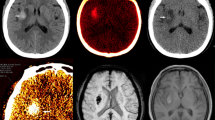

Stroke and gliomas had a strong impact on tHct (Fig. 5). All lesions led to a marked reduction in tHct whereas the contralateral striatum exhibited similar values across stroke, C6, 9LGS, and Control groups (18.0 ± 2.4 vs 28.5 ± 2.3%; mean across all lesions and contralateral striatum, respectively). Conversely, the Vv values differed between lesions (Fig. 5; Stroke: 1.1 ± 0.3%; C6 glioma: 3.4 ± 1.2% and 9LGS glioma: 8.2 ± 1.7%) as well as inside each glioma models (Fig. 5). Again, images from all animals (Supp. Figs 6–8) suggest excellent reproducibility.

(a) Representative images of anatomical images, diffusion (ADC), obtained by MRI, as well as, the vascular volume (Vv) and tissue hematocrit (tHct) maps, obtained by autoradiography, for the Stroke, C6 and 9LGS gliomas. All images are co-registered per animal. The white, green and dashed lines represent the lesion, contralateral and normal appearing areas. The white arrow represents a tHct hotspot inside the C6 glioma. (b) tHct values measured using the autoradiography (ARG) approach in lesion or in the healthy striatum for each pathological model (Stroke, 9LGS and C6 gliomas). (c) Histogram of tHct values measured by ARG in the stroke (black line), glioma 9LGS (red), glioma C6 (blue line) and Healthy striatum (green line; data from the 3 pathological groups were pooled) areas. Values are displayed as Mean ± SD.

In stroke, tHct decreased to 19.5 ± 2.5% two hours after stroke onset (p < 0.0001 vs striatum). This reduction was not homogeneous within the region with reduced ADC (from 852 ± 54 µm²/s in healthy striatum to 544 ± 57 µm²/s in the stroke lesion) and part of the reduced ADC region had no reduction in tHct (Fig. 5a, white dashed line and Fig. 5b, black line).

For the two glioma models, the mean reduction in tHct was similar to that of stroke (Hct became 18.5 ± 2.3% in the 9LGS glioma and 16.1 ± 1.2% in the C6 glioma; p < 0.00001 vs striatum). The lesion with the most spatially homogeneous reduction in tHct was the 9LGS, as observed on the maps (Fig. 5a) and highlighted by the histogram (Fig. 5c, red curve). In the C6 tumor, the reduction in tHct was more heterogeneous than in 9LGS with the presence of hotspots (Fig. 5a, white arrow) and lower tHct areas (Fig. 5c, blue curve). The ADC values in these two tumors at this stage of growth were 957 ± 76 µm²/s for the C6 and 862 ± 69 µm²/s for the 9LGS, values above that of contralateral striatum (757 ± 34 and 770 ± 60 µm²/s, respectively (p < 0.0002).